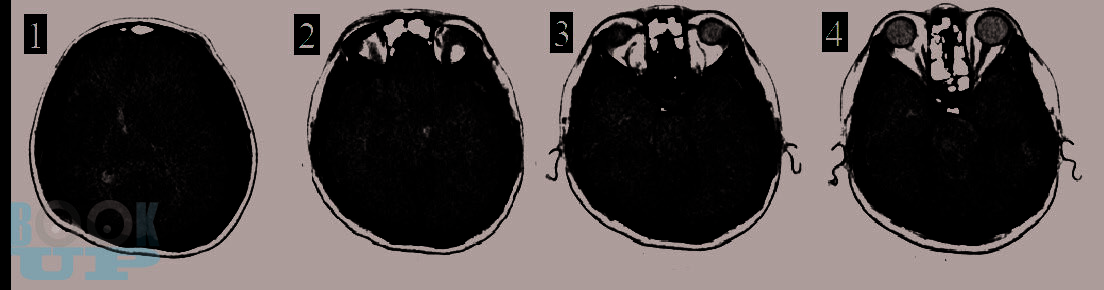

В этой книге мы рассказываем о динамике и взаимосвязи патологических процессов. Эти знания позволяют обосновать вашу тактику. В книге обсуждаются взаимосвязь первичного и вторичного повреждения мозга. Как внутричерепная гипертензия приводит к дислокациям и вклинениям головного мозга и/или нарушениям кровоснабжения мозга. Обсуждается регуляция тонуса сосудов мозга в норме и патологии. Зависимость церебрального перфузионного давления от среднего артериального давления, внутричерепного давления и сохранности ауторегуляции тонуса мозговых сосудов. Рассматриваем варианты отека мозга и возможности лечения. Мы рассказываем как на основе результатов мониторинга внутричерепного давления принимаются решения о том как лечить пациента.